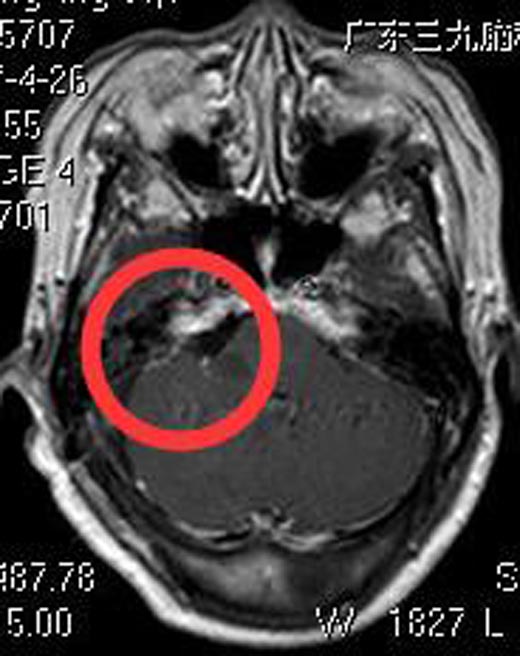

由鲁明主任主刀,在全麻下行右侧桥小脑角占位切除术,术中显微镜下见肿瘤位于右侧桥小脑角,质软,珍珠样,血供少,予分块切除,面、听神经保留完整,肿瘤全切。术后叶奶奶没有面瘫、吞咽困难、饮水呛咳等后组颅神经损害症状。术后病理回报:神经鞘瘤。

▲手术后